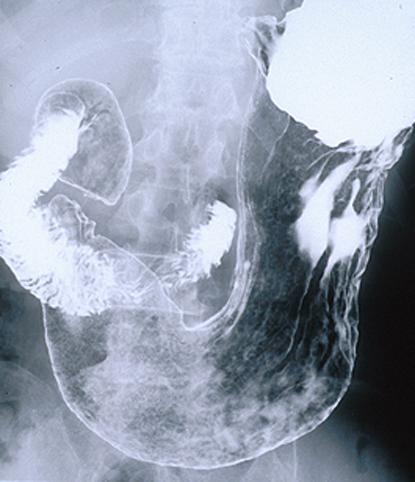

Criteria of Hist.ClassificationMalignant Lymphoma/MLP type

LocationStomach/Body

Technique, MethodX-ray

Size15 - 19